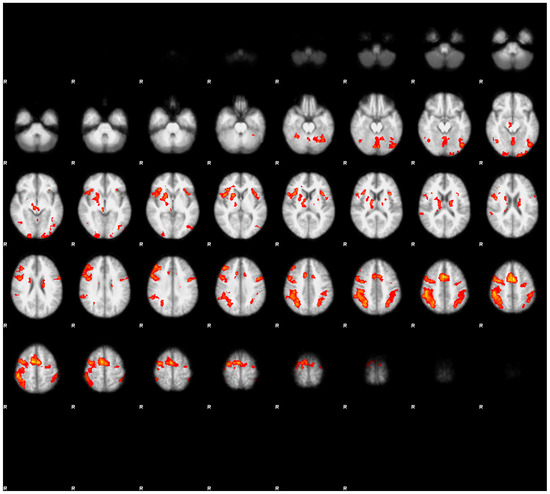

3.3.1. Main Effects of the Task in Both Conditions

The results are displayed in Figure 2 and Figure 3, as well as presented in Table 3 and Table 4. In both conditions, we observed a mostly overlapping pattern of activations in the lateral frontal, lateral parietal, and medial frontal regions. In both conditions, we also observed overlapping clusters in the left lateral temporo-occipital regions. There were marked differences between both conditions. In the rested condition, the general extent of suprathreshold activation was notably wider and more bilateral than in the fatigued condition. The strongest effects of task in the rested condition were observed in the posterior parietal cortex, as well as in the premotor cortex, extending into the dorsolateral cortex, mainly in the right hemisphere. Bilateral activations were also observed in the anterior insulae and in the medial frontal regions (SMA). In contrast with the fatigued condition, we observed bilateral activations in the polar visual cortex, as well as in the fusiform gyrus.

In the fatigued condition, the extent of the suprathreshold clusters was notably smaller. Bilateral activations were seen only in the parietal regions, while in the frontal regions, the activations were mainly observed in the right hemisphere. In neither condition were the activations correlated with the reaction times.

Figure 3. The main effects of the task in the fatigued condition. Images were thresholded at Z > 3.1. Note the more extensive activations in the right hemisphere of the brain (denoted by the letter R) in the posterior parietal cortices, supplementary motor area (SMA), premotor cortex, and dorso-lateral prefrontal cortex in comparison to the rested condition (see Figure 2). Activation in the middle temporal cortex maintained its lateralization in the left hemisphere.

Energies 14 05409 g003